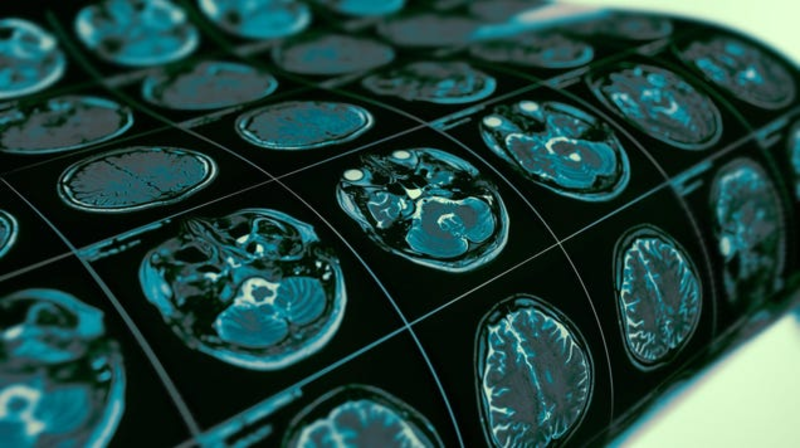

You're Practically Guaranteed to Get Alzheimer's If You Have This Genetic Variant

A team of scientists seems to have discovered a previously hidden genetic cause of Alzheimer’s. In a new study Monday, the researchers found strong evidence that people carrying two copies of a genetic variation already tied to Alzheimer’s risk are practically destined to develop the neurodegenerative disorder as they…